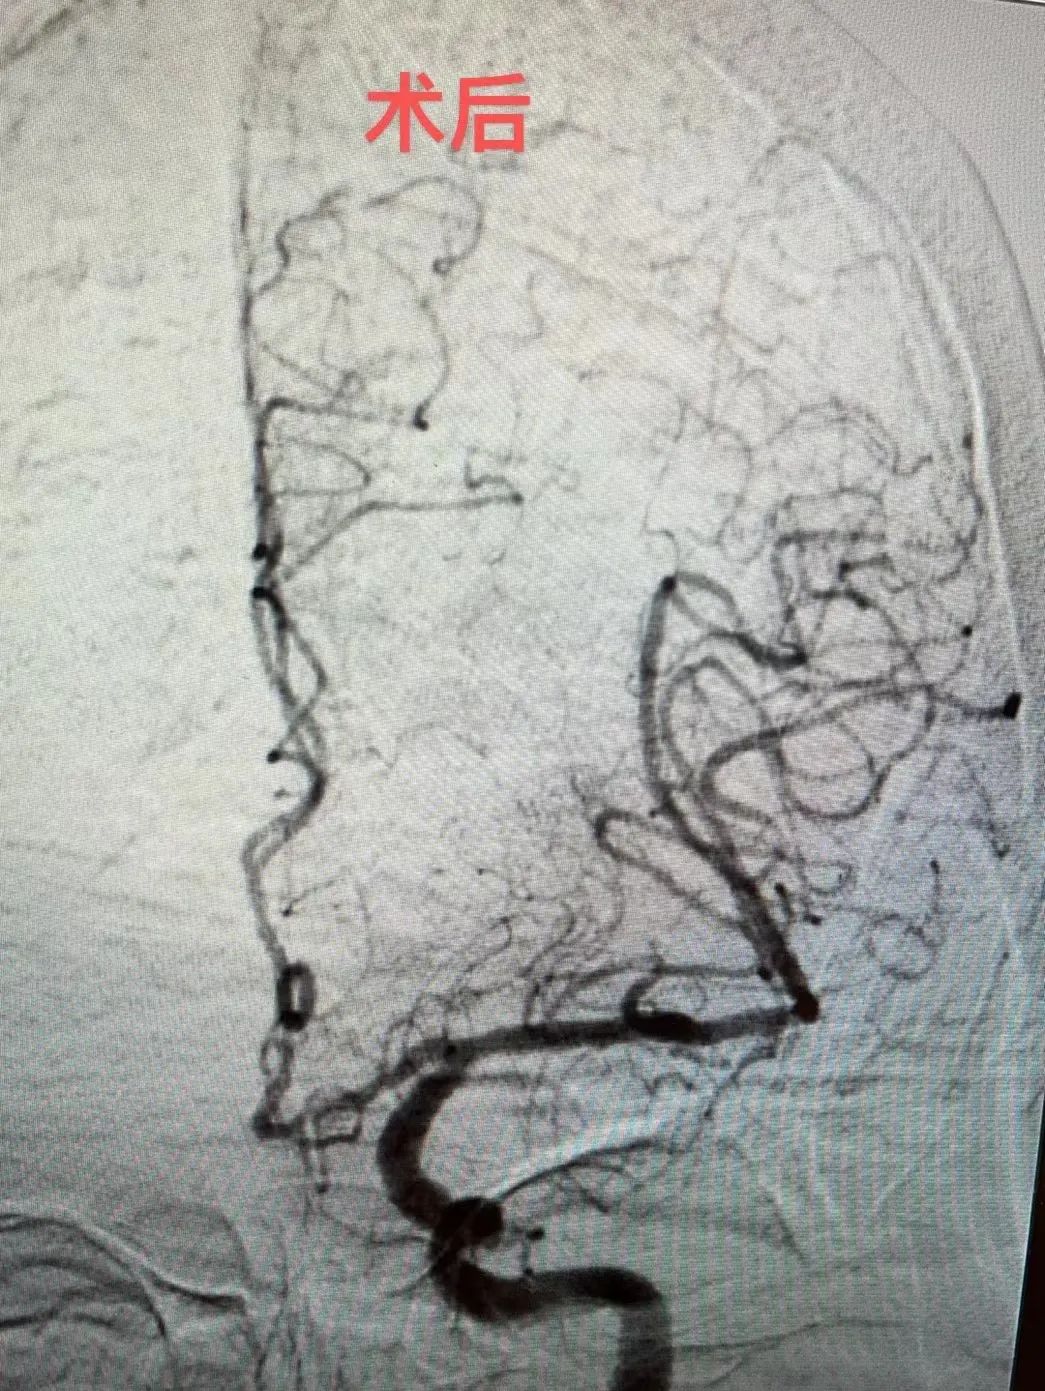

介入导管室一键启动,麻醉科配合采用局麻+药物联合麻醉,缪桂华副主任医师带领团队通过股动脉置管建立手术取栓通道,考虑血栓负荷量大,小心探查,由近及远行ADAPT技术抽吸出血栓主体,颅内残余血栓采用抽吸导管及支架钳夹出来,最终在错综复杂的血管“迷宫”中,找到了一条“生命通道”,手术时间仅用1小时左右,石奶奶被收住入神经内科监护病房继续救治。

图片

当晚,就在术后2小时左右,石奶奶慢慢清醒过来,她说话顺畅,手和脚活动都恢复正常,得知这一消息的石奶奶家人们欣喜万分、泪流满面。